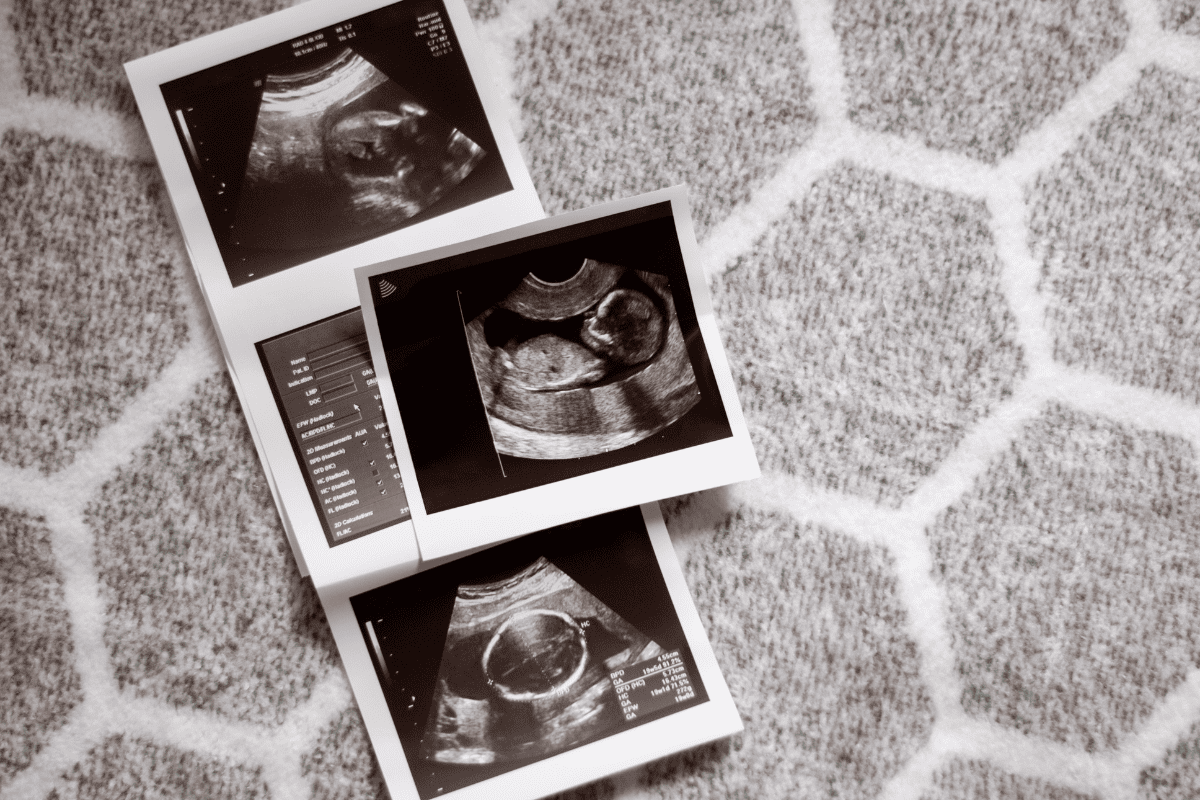

УЗИ скрининг 2 триместра проводится трансабдоминальным способом — через переднюю стенку живота с помощью специального датчика, но при необходимости дополняется интравагинальным обследованием. Врач оценивает анатомию плода, размеры внутренних органов, структуру головного мозга, сердца, почек, позвоночника, а также состояние плаценты, количество околоплодных вод, длину шейки матки. Особое внимание уделяется выявлению пороков развития и соответствию размеров плода гестационному возрасту.